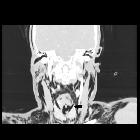

laryngotracheales Trauma

CT

Features include :

- disruption of the tracheal or bronchial cartilage rings

- irregularity of the airway wall

- focal thickening of the tracheal or bronchial wall

- laryngeal disruption

- massive pneumomediastinum (sometimes despite appropriate pleural space decompression with intercostal catheters)

- fallen lung sign (first described in 1970 ): rare

CT is the modality of choice. Review of airway obstruction includes evaluation of edema, hematoma, foreign body or displaced fractures.

CT review for larynx function should also include close inspection for lacerations especially to the vocal cord and anterior commissure, and arytenoid cartilage dislocation or avulsion.